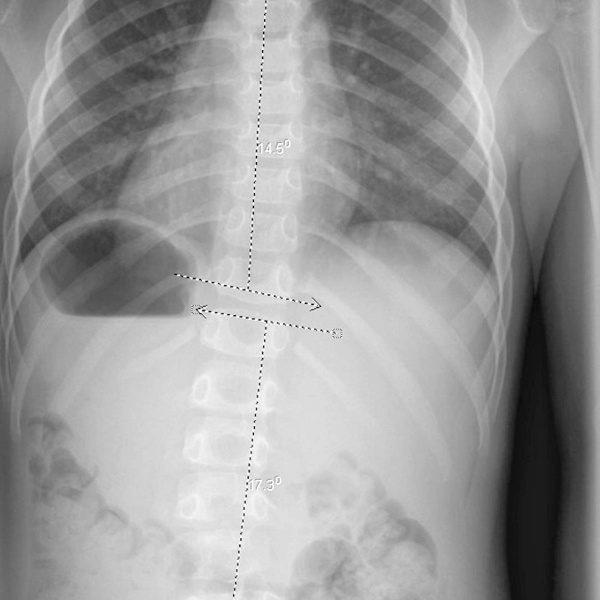

Una niña de 5 meses fue diagnosticada de ausencia congénita bilateral de pedículos L4 y de riñón derecho ausente. Desarrolló una escoliosis torácica derecha a los 3 años que fue tratada con un aparato ortopédico. En su seguimiento más reciente a los 16 años, estaba esqueléticamente madura y tenía una escoliosis torácica derecha residual de 20 °. No tenía dolor, tenía un examen neurológico normal y estaba completamente activa.

Este caso presenta un seguimiento a largo plazo de un paciente con ausencia congénita bilateral de pedículos L4. Ella desarrolló escoliosis que fue tratada con éxito con aparatos ortopédicos. No se desarrollaron otros problemas importantes durante los 15 años de seguimiento.